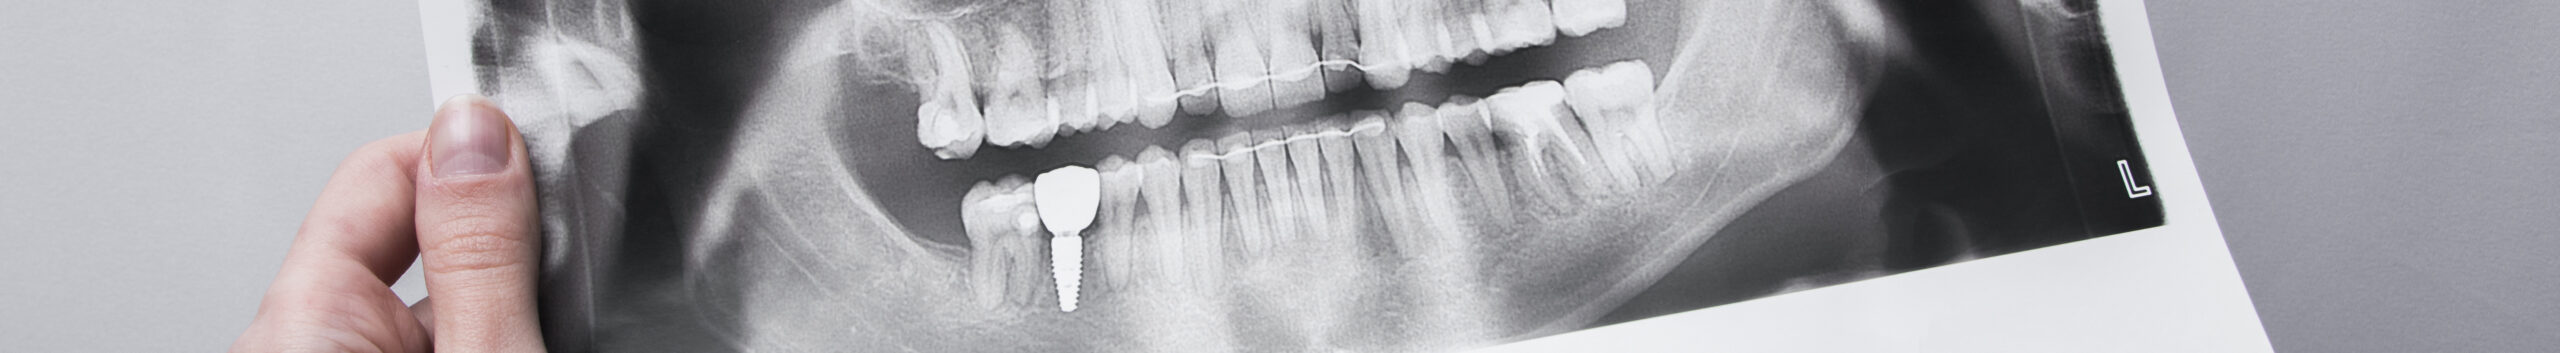

Панорамный снимок зубов – рентгеновское исследование, позволяющее получать двухмерное изображение нижней и верхней челюсти.

1. Панорамный снимок (ортопантомограмма, ОПТГ). Двухмерное изображение верхней и нижней челюсти. Развернутый снимок помогает оценить состояние ретинированного зуба, кисты, пломбы, нижнечелюстного состава, гайморовой пазухи. У врача появляется возможность составлять подробный план лечения, имплантации и протезирования. Разрешается проводить обследование в любом возрасте.